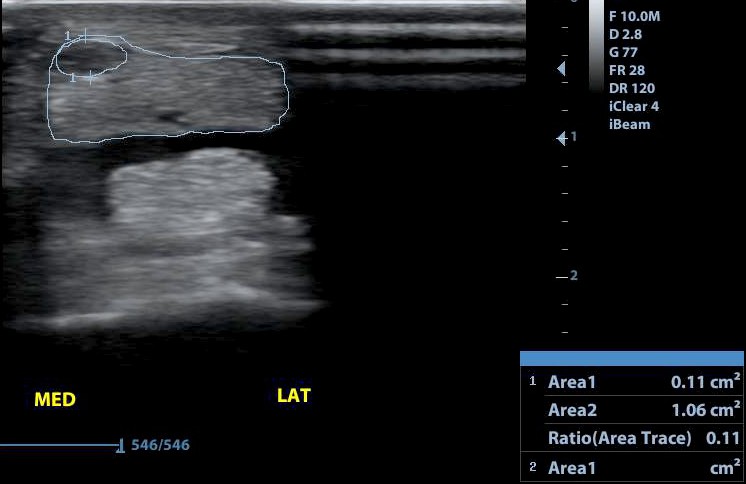

A mély ujjhajlító ín csüd alatti sérülése bejelölve. A mérés alapján a keresztmetszet 11 százalékát érintő sérülés.

A mérések azt mutatják, hogy a sérült bal oldal jelentősen megvastagodott az ép oldalhoz viszonyítva. Fontos az aszimmetrikus alak felismerése is!